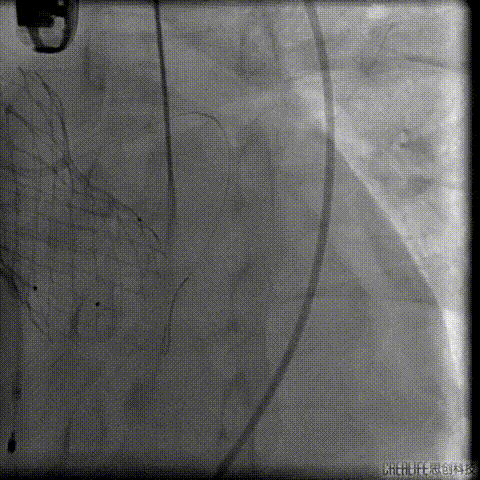

导丝跨瓣及测压

此时患者出现室速 血气提示代谢性酸中毒、高钾血症,予电复率、补碱、补镁、碘氨酮等治疗后恢复窦性心律。

预扩主动脉瓣

左冠血流受到影响

予ECOM支持

患者恢复自主心率